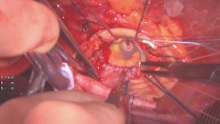

The patient had severe aortic stenosis with heart failure symptoms. Peak and mean gradients across the aortic valve (AV) were 71 and 40 mmHg, respectively. A preoperative CT angiogram (CTA) showed a root of 34 mm, an ascending aorta of 39 mm, and severe longitudinal calcification of the ascending aorta. A median sternotomy was performed with aortic cannulation at the distal ascending and proximal arch. A complete transverse aortotomy was made approximately 2 cm above the sinotubular junction (STJ) anteriorly and 1 cm above the STJ posteriorly. The aortic root was dissected above the left and right atrium to the level of the dome of the left atrium and the nadir of the noncoronary sinus. The annulus was measured to be 23 mm. A standard Y-incision was made at the left –non-commissure, extending from the aortotomy into the aortomitral curtain, underneath and parallel to the aortic annulus to their respective nadirs, by partially cutting into the left and right fibrous trigones. A 2 x 3 inch (5 x 7.5 cm) rectangular-shaped Hemashield Dacron patch was trimmed to a width 5 mm greater than the distance between the two cusp nadirs on each end.

This patch was sewn to the aortomitral curtain and mitral annulus from the left fibrous trigone to the right fibrous trigone with a running 4-0 Prolene suture. The suture line was transitioned to the aortic annulus at the nadir of both the left and noncoronary sinuses, sutured along the longitudinal length of the patch to the level of the transverse aortotomy incision, and secured with additional 4-0 Prolene sutures. The valve sizer was placed in the enlarged root, touching all three nadirs of the aortic annulus to determine the size of the prosthesis, which was found to be size 29.

The height of the divided left noncommissure was marked on the patch to indicate where the highest suture should be placed, and the size 29 valve sizer was then traced onto the patch. While the patch was pulled upward, the size 29 bioprosthetic valve was placed into the enlarged aortic root with one strut facing the left-right commissure to confirm that the marking of the valve sutures on the patch matched the sewing ring of the bioprosthesis, and the two coronary ostia were not obstructed.

Nonpledgeted 2-0 Ethibond sutures were then placed along the native aortic annulus in a noneverting fashion. The size 29 valve was placed with one strut facing the left-right commissure, and the valve sutures were divided by three and evenly distributed to the sewing ring of the three cusps of the bioprosthetic valve, starting at the left-right commissure. The sutures at the nadirs of the noncoronary and left coronary sinuses, the lowest point of the aortic annulus, were tied first. A longitudinal aortotomy was made in the posterior proximal ascending aorta, and the distal end of the rectangular patch was trimmed in a triangular shape symmetrically, with the tip of the triangle 2-3 cm above the strut. The aortotomy was closed with 4-0 Prolene, incorporating the triangular-shaped end of the patch into the longitudinal aortotomy using the “Roof” technique (3).